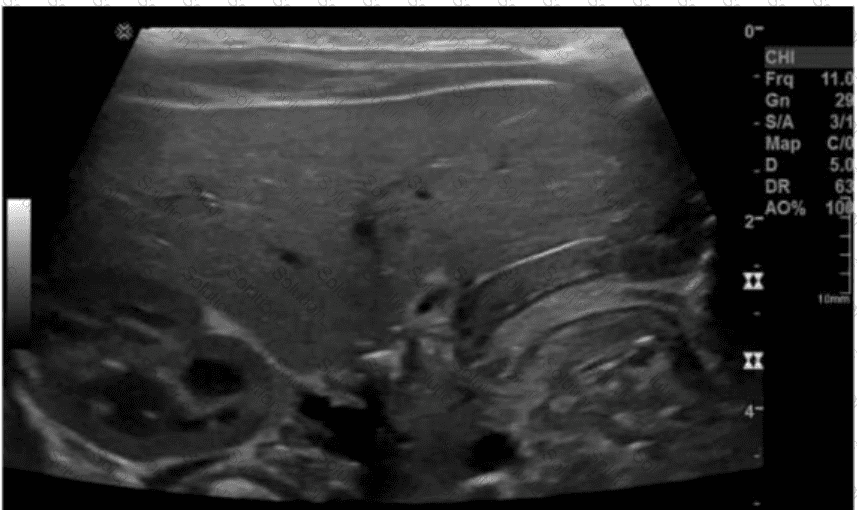

Which condition of the transplant kidney is indicated by the arrows on these images?